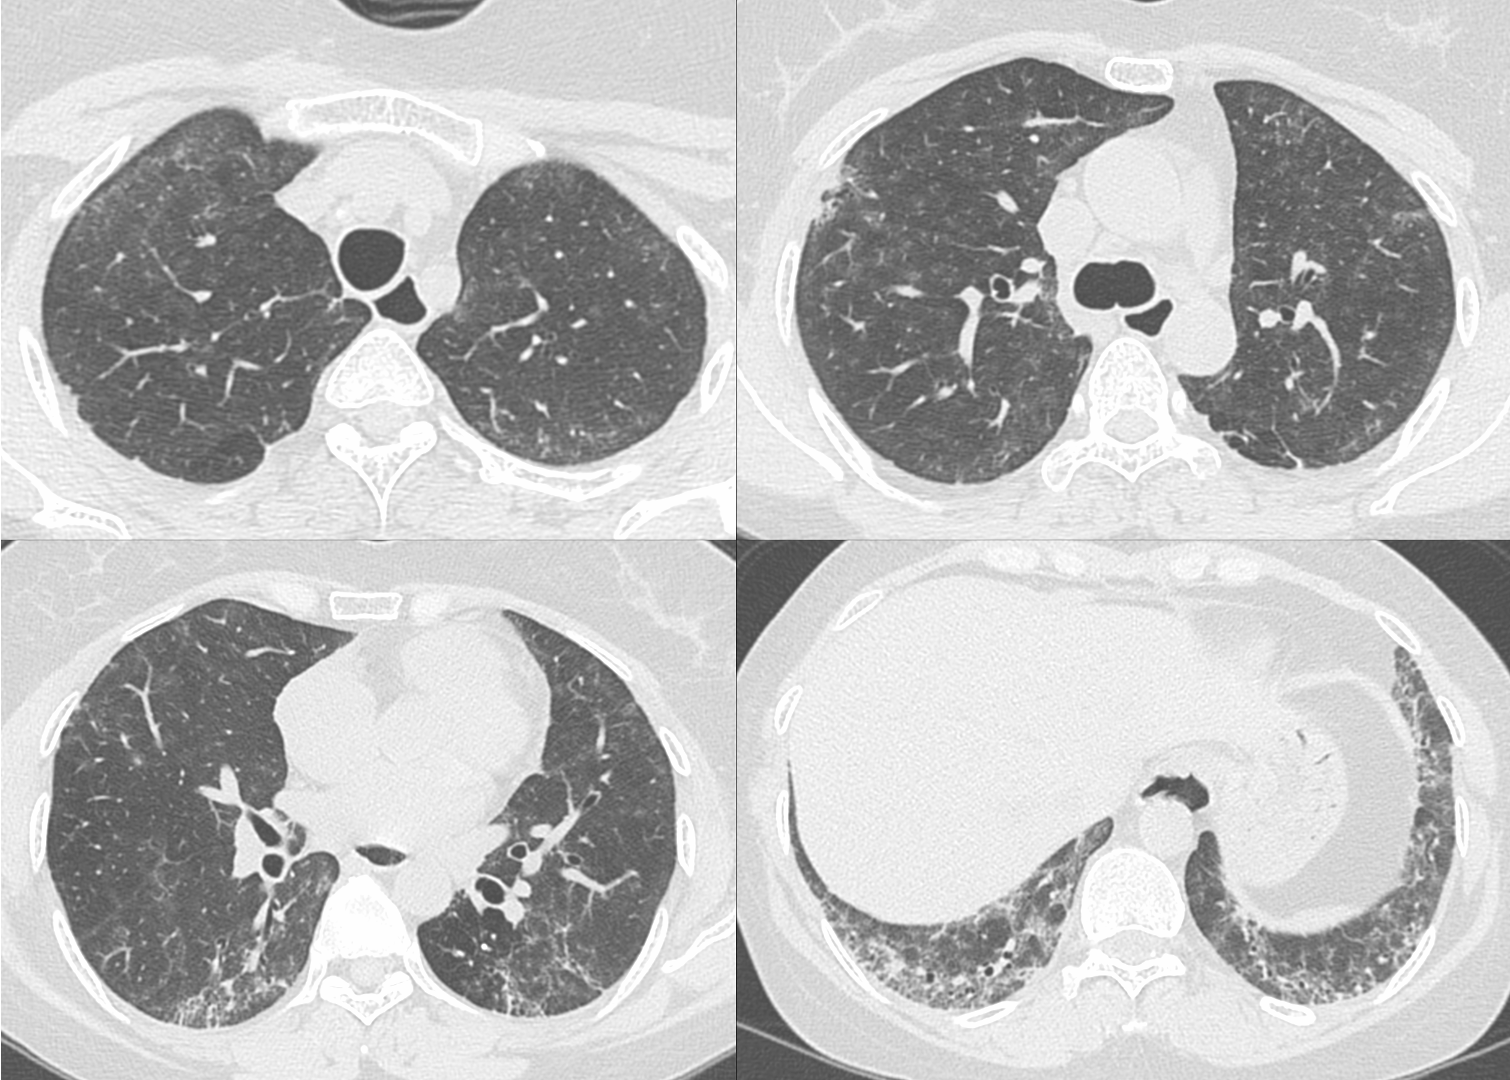

33-years old with scleroderma and scleroderma ILD with a fibrotic non-specific interstitial pneumonia (NSIP) pattern.

The upper lobes show interstitial lesions, typically considered to be part of the NSIP pattern.

A recent Japanese paper introduces the concept of FANO - faint amorphous nodular opacities - first described with asbestosis, which are seen typically in the anterolateral non-dependent upper lobes and most commonly associated with an NSIP pattern and are known to progress and likely represent early-stage interstitial disease.

This brings to focus the likelihood that the early stage scleroderma ILD cases I have shown earlier have also likely been FANO lesions.